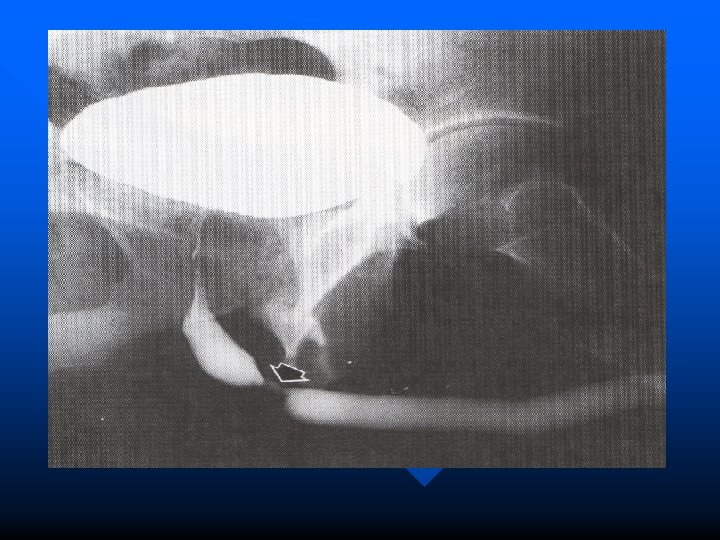

Imaging § retrograde urethrography § urethrogaphy bipolar/voiding urethrocystography § IVU ( upper urinary tract evaluation and pelvic bone)